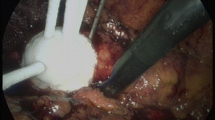

The success of RFA depends on a temperature-based algorithm and treatment endpoints detected by temperature monitors, temperature probes and impedance probes [12]. We recommend that a temperature goal of at least 60 °C be obtained in order to achieve instantaneous irreversible cell damage by denaturation of proteins and coagulative necrosis (Fig. 6.1). General, conscious and intravenous sedation are anaesthetic options for RFA procedures; general anaesthesia is ideal. Under general anaesthesia, the respiratory cycle can be manipulated allowing for more accurate probe placement [1, 5].

Gross image (confirmed histologically) demonstrating complete destruction of 4.7 cm left renal clear cell carcinoma via coagulative necrosis. The kidney removed at 12 months follow-up after being treated successfully by laparoscopic RFA, Cool-tip® (Valley Lab, Boulder, CO, USA) under laparoscopic US image guidance